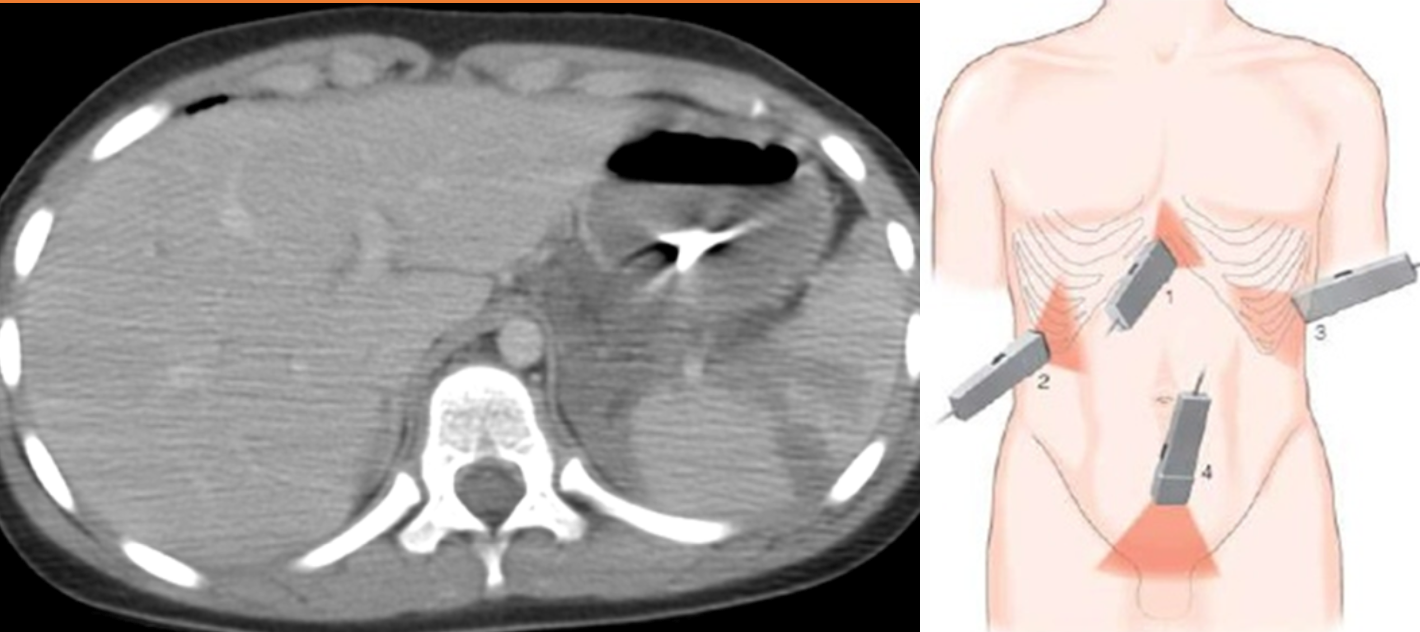

(Image: Splenic injury (CT scan))